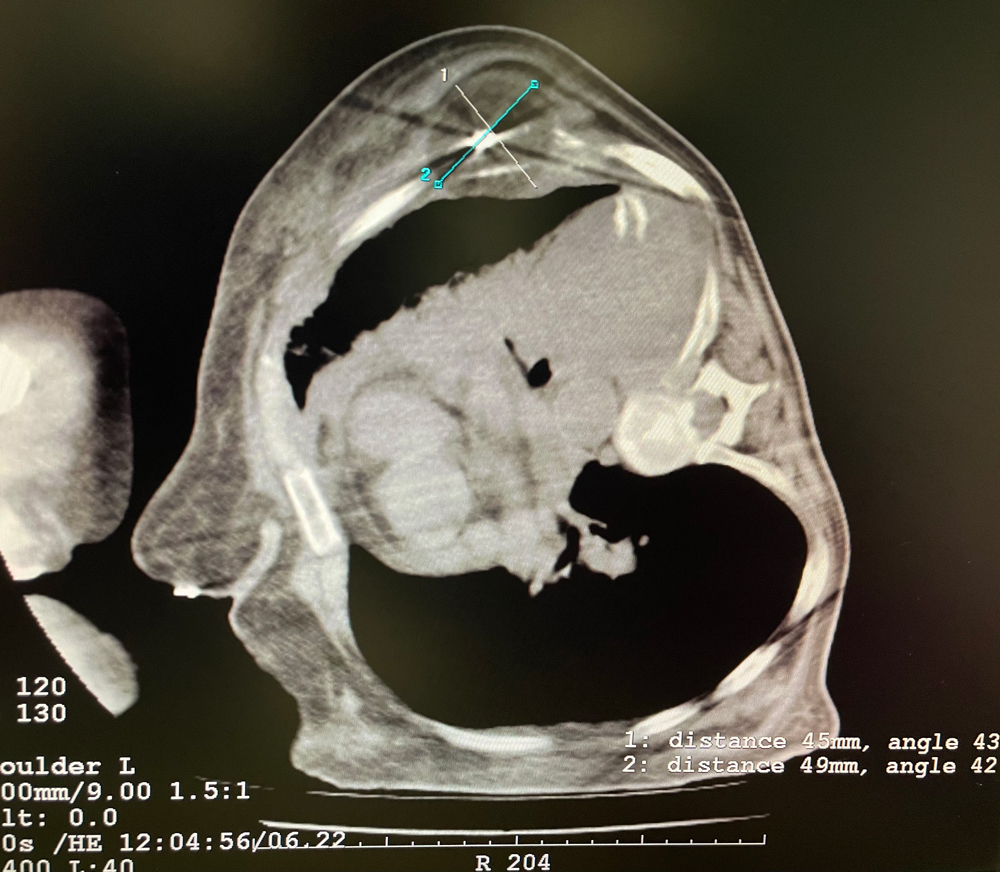

女,56歲,肺轉(zhuǎn)移瘤,骶骨、左側(cè)肋骨各一轉(zhuǎn)移灶,病灶大小均為5cm。骶骨轉(zhuǎn)移灶、肋骨轉(zhuǎn)移灶各進行2個凍融循環(huán)。患者術(shù)后狀況良好。